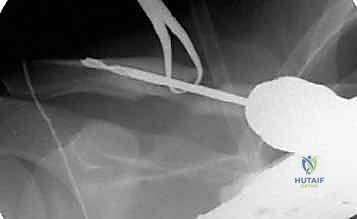

في تقنية التثبيت داخل النخاع، يتم استغلال هذه القناة الطبيعية لتمرير المسمار أو القضيب المرن بداخلها، مما يجعل المسمار يعمل كدعامة داخلية (Internal Splint) تتحمل الأحمال وتشاركها مع العظم (Load-sharing)، بدلاً من تحملها بالكامل كما تفعل الشرائح المعدنية الخارجية (Load-bearing).

هذه هي التقنية المتقدمة التي يتميز بها البروفيسور محمد هطيف. بدلاً من وضع شريحة خارجية، يتم إدخال مسمار أو قضيب مرن (مثل مسمار التيتانيوم المرن TEN أو مسامير مصممة خصيصًا للترقوة) داخل تجويف العظم (القناة النخاعية).